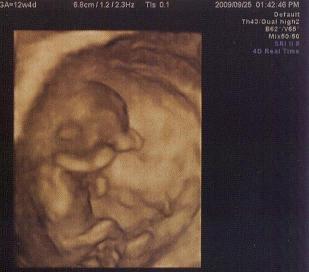

Kép Picurink-12. hét

Íme az UH-n készült kép a mi kis picikénkről! :)

Kép